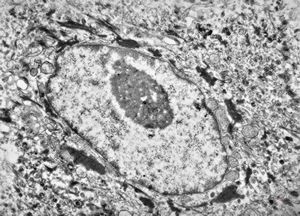

M, 70y. | mycosis fungoides - Sézary cell

M, 70y. | mycosis fungoides - Sézary cell